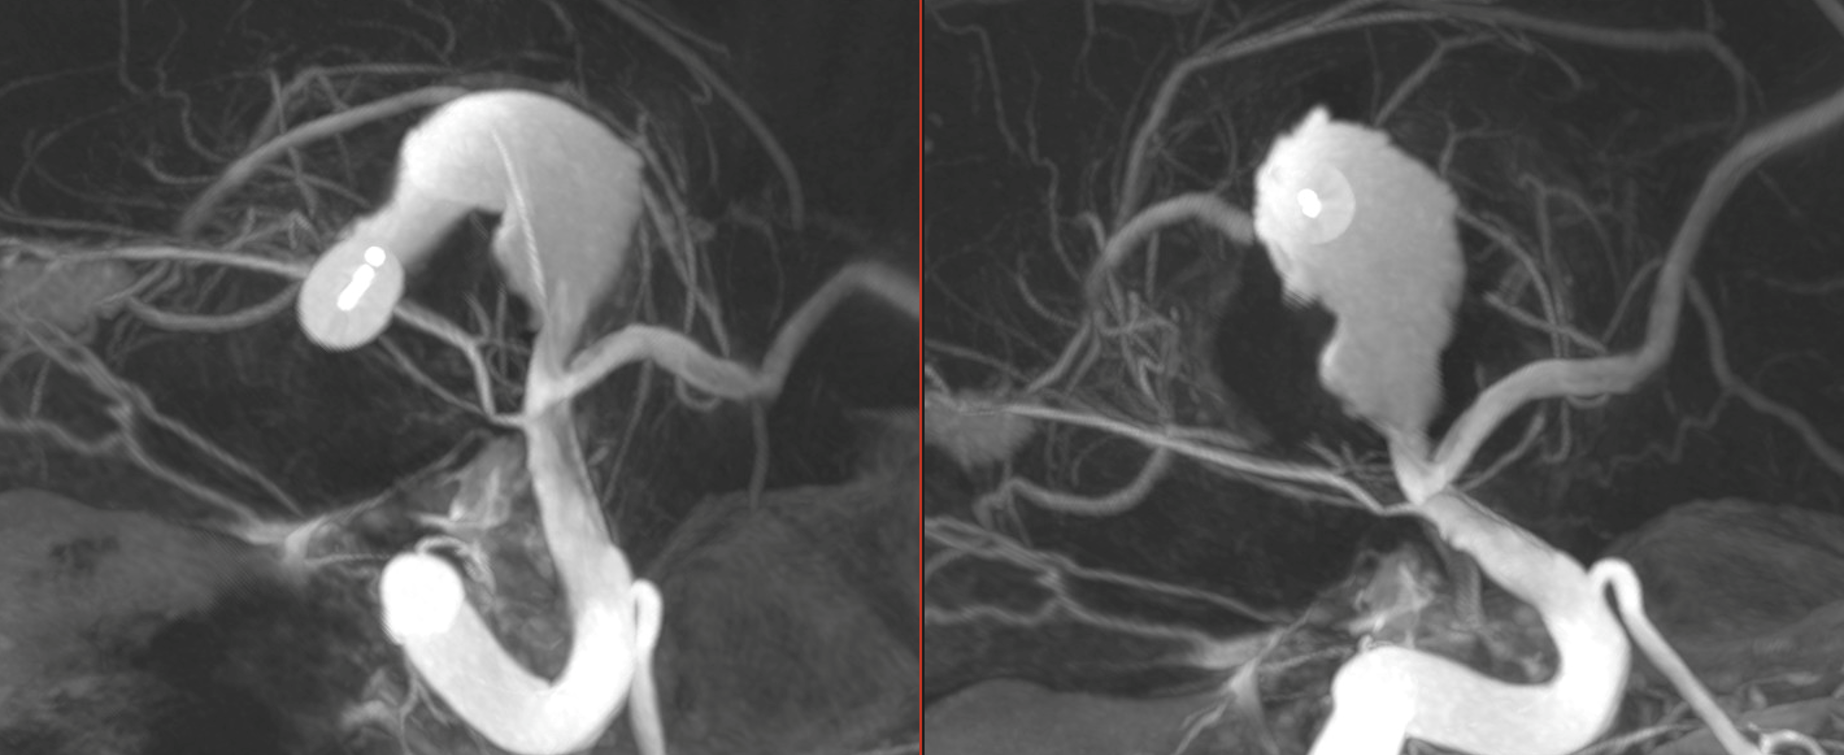

A patient presenting with a giant serpentine MCA aneurysm. The plan was to do a high flow ECA-MCA bypass and then coil occlude the MCA

Immediately after bypass